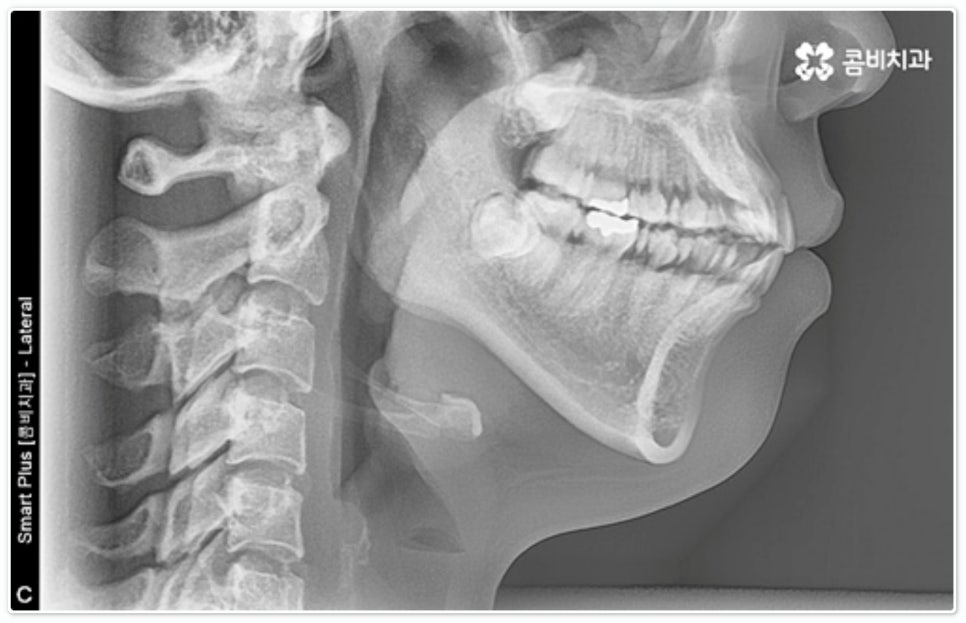

개개인의 치아와 잇몸 상황, 치열과 골격 상태, 교합 등을 자세하게 검진해 본 후에 부정 교합의 문제가 크지 않고 발치가 필요하지 않아 비교적 적은 힘으로도 치아 이동이 가능한 경우에 부분 교정 을 고려해 볼 수 있는 거예요. 즉 어금니 교합이 정상이고 턱관절 문제가 크게 관련되어 있지 않으면서 앞니의 각도만 뻐드러진 경우나 앞니 사이가 살짝 벌어진 경우와 같이 원인이 앞니에만 국한된 경우에 앞니부분교정 치료를 진행할 수 있으므로 정밀 검진과 충분한 상담이 선행될 필요가 있어요.

그렇지 않고 전후방 각도 조절 또는 단순 횡적인 움직임으로 치열 개선이 가능한 케이스는 부분 교정을 진행하는데, 사진에서 보시는 사례가 바로 그런 경우에 속하고 있습니다. 앞니 6개에만 브라켓을 부착하였는데 보시다시피 치아 색상과 유사한 세라믹 재질의 장치를 이용하여 심미성 또한 높여 주었음을 알 수 있어요.